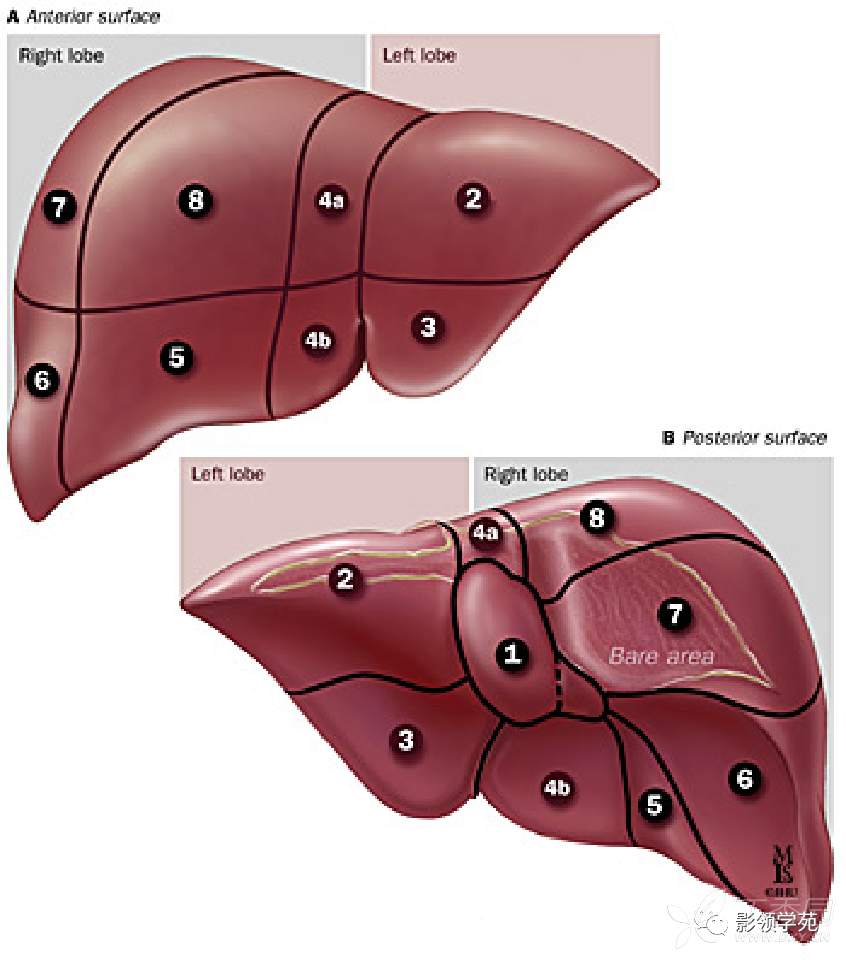

肝的分叶、分段

根据肝外形的沟裂将肝分为左、右、方、尾4叶的形态学解剖方法,因不符合肝内管道系统的分布规律,不能适应肝切除和影像学描述的要求。

肝脏的分叶和分段在临床上对于描述病变位置,确定治疗方案、特别是肝的切除范围,以及肝肿瘤的选择介入治疗等方面都有重要意义。

肝的功能解剖则是按照肝内Glisson系统和肝静脉的分布规律,并结合某些外形标志来分段分叶的。

Glisson系统即肝门静脉、肝动脉、胆管在肝内的分、属支被结缔组织纤维鞘包绕而形成的三联管道系统,似树枝状分布于肝内。

肝段就是以Glisson 系统为中心,包括其所属血供和胆汁引流的肝组织所构成的一独立的“功能”单位。

分段具体方法

3支主肝静脉将肝分隔成4个部分。

左、中、右3支主肝静脉走行区所形成的纵形切面(称为肝静脉裂)将肝分隔成4个部分,称为四个扇区。

每个扇区又被门静脉左、右支的水平切面分成上下2段。

4个扇区不包括尾状叶。

尾状叶编为Ⅰ段,它是一个自主段,因它不依赖于4个肝门静脉蒂和3支主肝静脉。

尾状叶同时接受来自左右肝门静脉和肝动脉的分支供血,其静脉血经肝小静脉直接回流入下腔静脉。

肝脏被正中裂分左、右半肝,左、右半肝又分为四部。

左半肝分内、外两叶,右半肝分前、后两叶

门静脉左、右支充当横裂,将四部又分为八段。

前面观

下面观

记忆:

第一肝门以上顺时针:7 8 4 2

第一肝门以下顺时针:6 5 4 3

整个的分段,顺时针走向 2、3、4、5、6、7、8